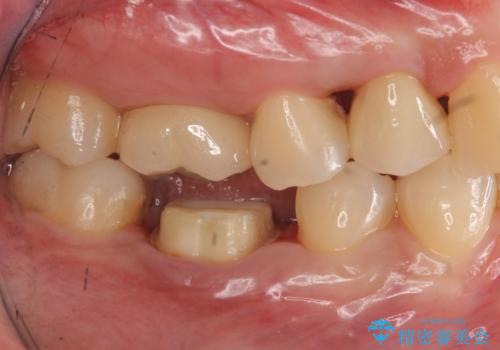

- 他の歯を治療中にレントゲン写真を撮ったところ虫歯を発見。

どうせなら1つ奥の銀歯も白くしたいとのご希望があり、2本ともセラミックにて治療をしていくことになりました。

虫歯治療に加え、奥の銀歯も同時にやり替えました。

精度の良いクラウンにやりかえることは今後の虫歯リスクを減らすことにつながります。